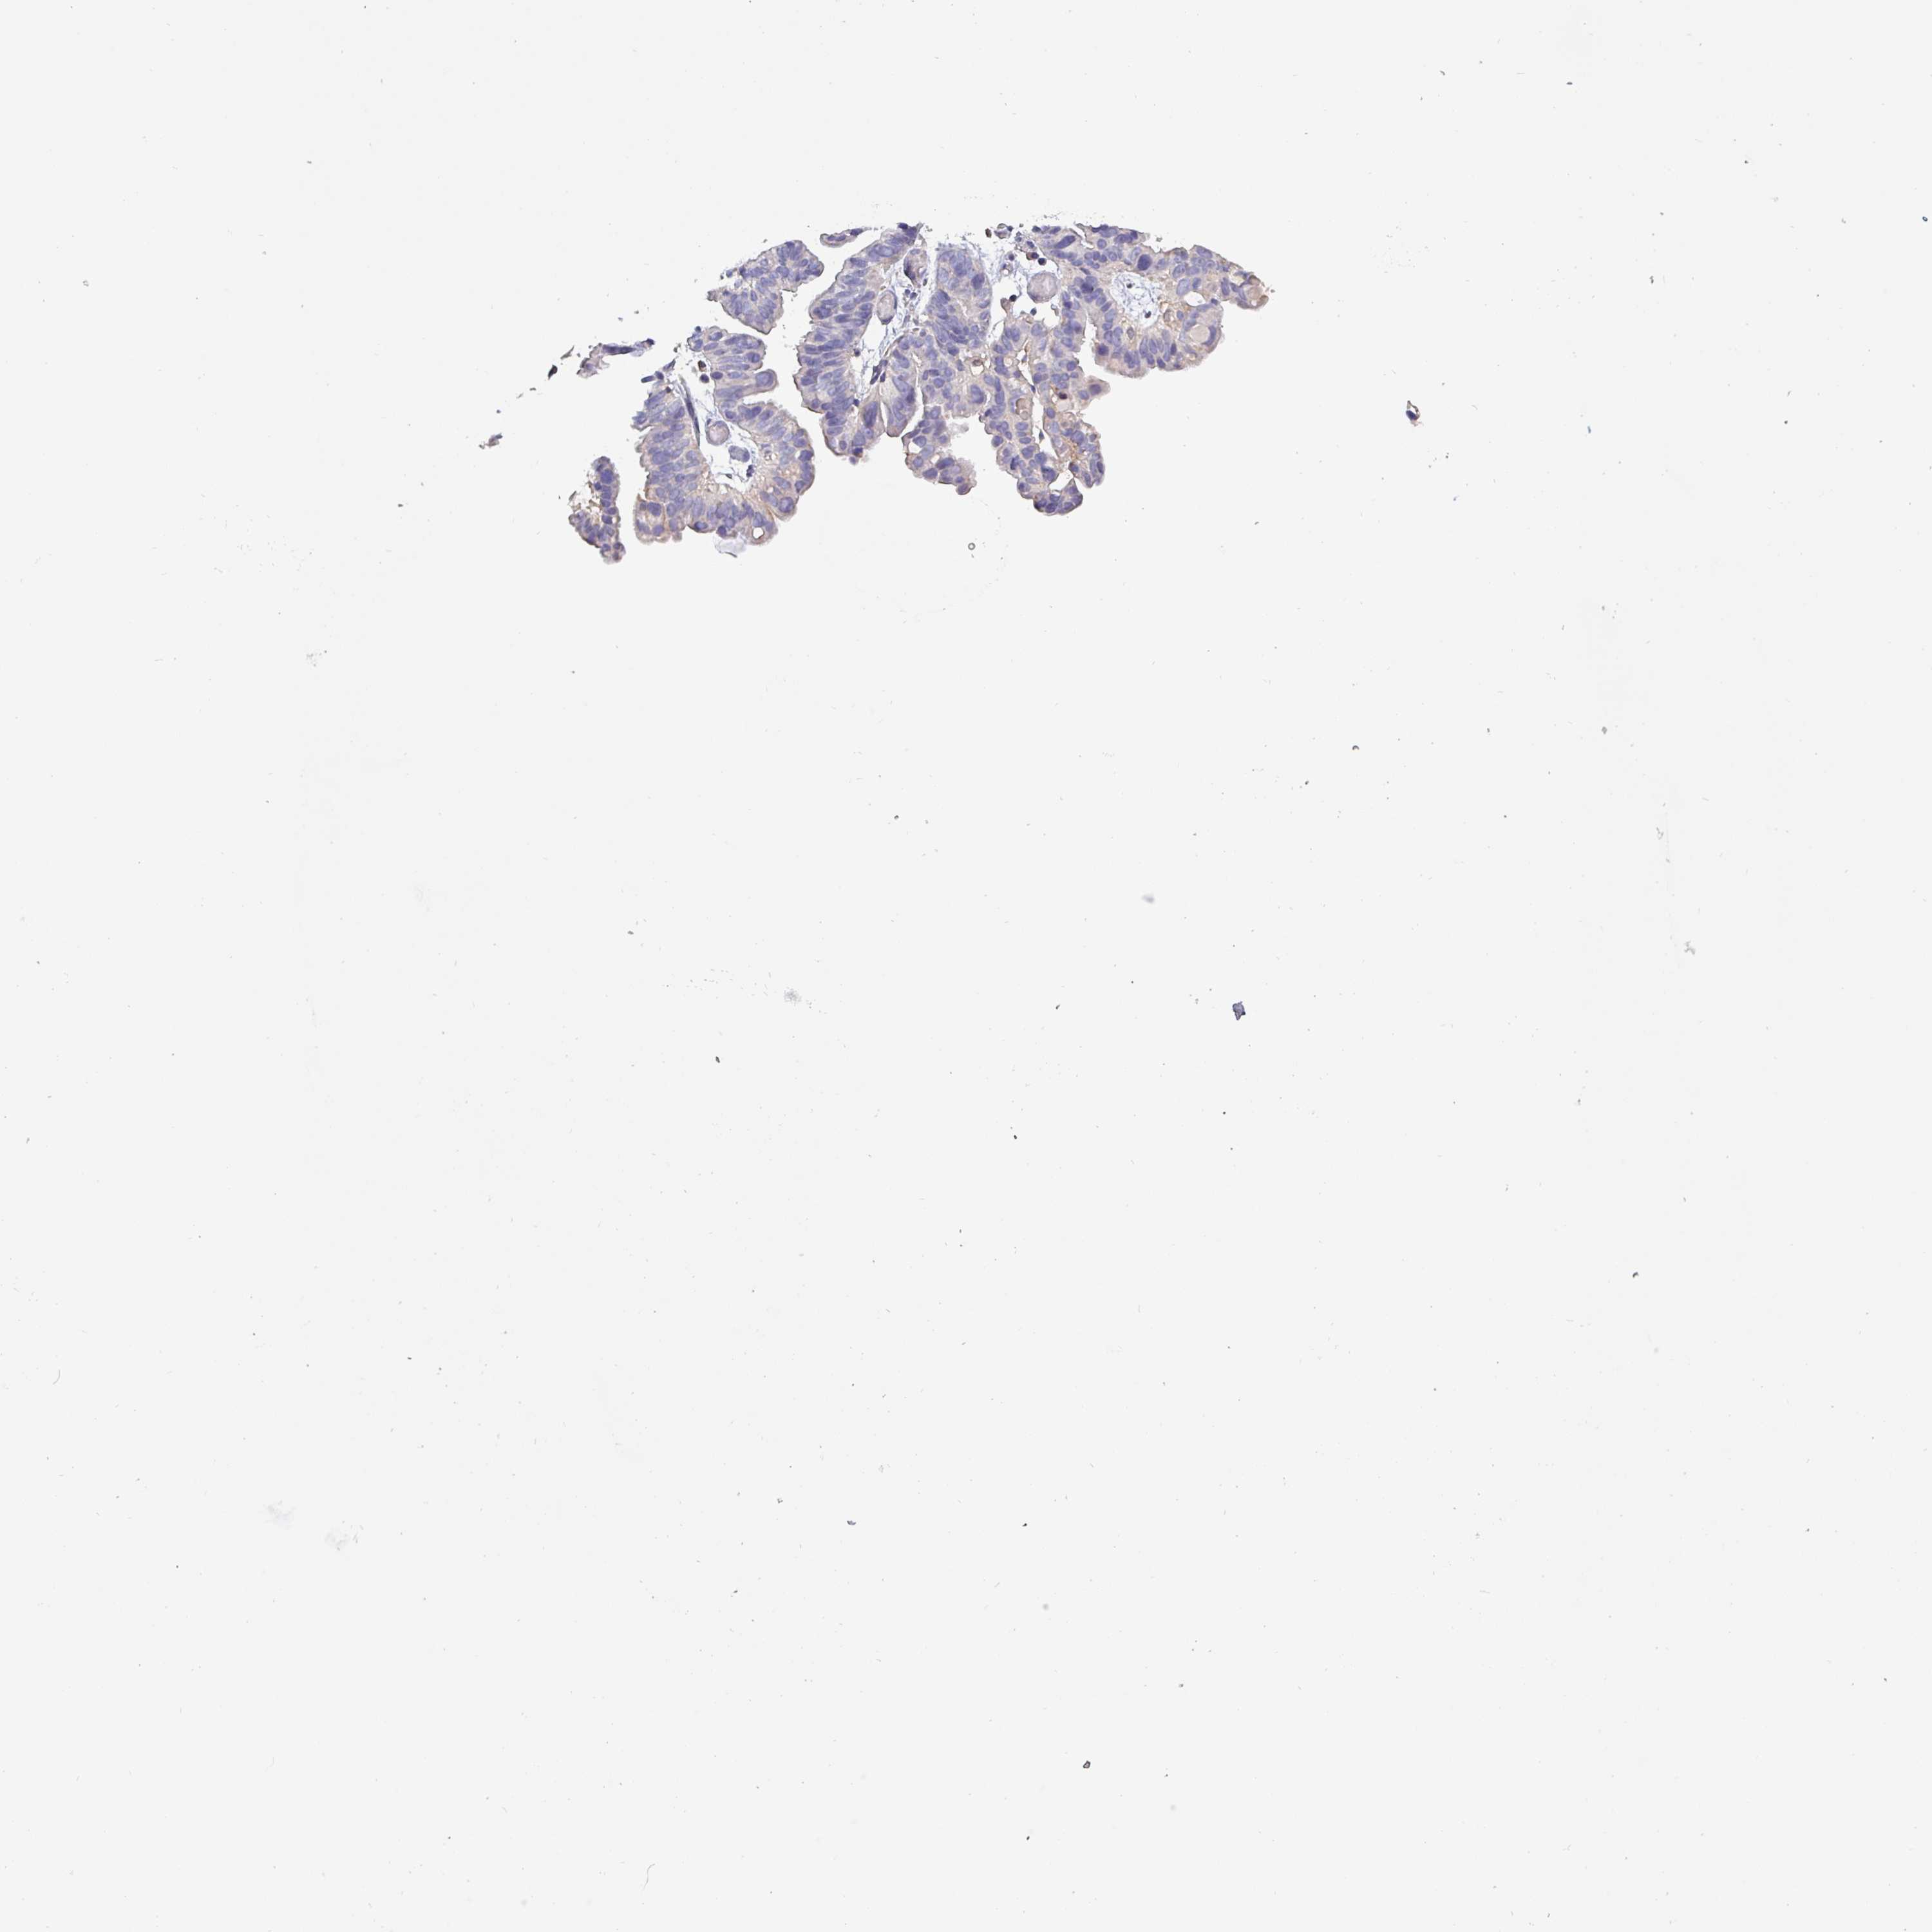

OVARIAN CANCER - Protein expressioni

A mouse-over function shows sample information and annotation data. Click on an image to view it in a full screen mode. Samples can be filtered based on level of antibody staining by selecting one or several of the following categories: high, medium, low and not detected. The assay and annotation is described here.

Note that samples used for immunohistochemistry by the Human Protein Atlas do not correspond to samples in the TCGA dataset.

Antibody stainingi

Antibody staining in the annotated cell types in the current human tissue is reported as not detected, low, medium, or high, based on conventional immunohistochemistry profiling in selected tissues. This score is based on the combination of the staining intensity and fraction of stained cells.

Each image is clickable and will lead to virtual microscopy that enables deeper exploration of all samples and also displays staining intensity scores, fraction scores and subcellular localization as well as patient and tissue information for each sample.

Antibody HPA045402

Cystadenocarcinoma, serous, NOS

Carcinoma, endometroid

Cystadenocarcinoma, mucinous, NOS

Carcinoma, NOS